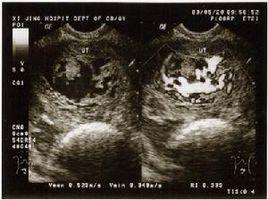

小婷腹部日渐隆起,7月底,小婷怀孕六个多月,突然出血了,量还很大。丈夫吓坏了,赶紧把她送到了东阳市人民医院。检查结果却让人大跌眼镜,B超检查显示,子宫内充满了水泡状的东西,就跟葡萄一样,根本没有胎儿,这就是常说的葡萄胎。

医生解释说,小婷这种情况属于妊娠后胎盘绒毛滋养细胞增生,间质高度水肿,形成大小不一的水泡,水泡间相连成串,形状就像葡萄一样。发病率大约为1/1000。换句话说,就是胎儿没正常发育。

6、目前B超检查能够帮助医生更早地诊断出葡萄胎。在闭经8周前后,B超监测,未发现有胎囊、胎心及胎儿。孕周、甚至18周仍不感有胎动,听不到胎心。B超扫描显示雪片样影像而无胎儿影像。